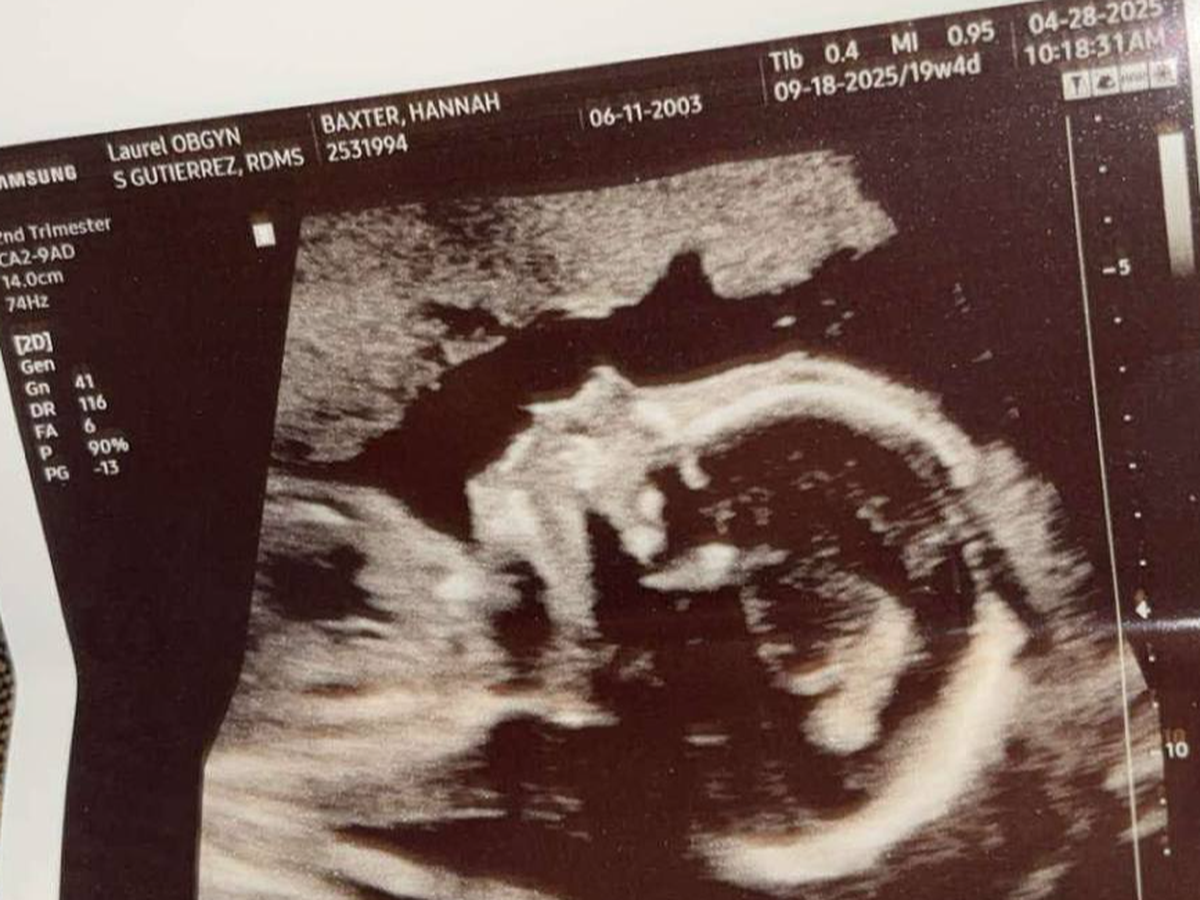

This past Monday, I went to the OB for my 20-week ultrasound with a mix of excitement and anxiety. After experiencing a miscarriage last year, I had no idea what to expect, but I tried to keep a positive mindset, especially since I was about to see my beautiful baby. The ultrasound tech was amazing, explaining everything and reassuring me that things looked great—until she said something I never imagined I’d hear.

She gently asked, “Do you remember what your daughter’s ultrasound looked like?” I replied, “Kinda, not really, haha.” Then, I sensed something was off. She paused and said, “I’m so sorry to tell you this, but your baby has only the right side of her heart. It’s called hypoplastic left heart syndrome.”